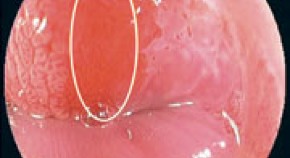

Gastric polyps are a heterogeneous group of lesions that have differing consequences for patients, particularly in terms of malignant potential. However, there is currently no consensus for the management of patients with these polyps. The British Society of Gastroenterology has, therefore, published objective management guidelines for patients with these lesions.